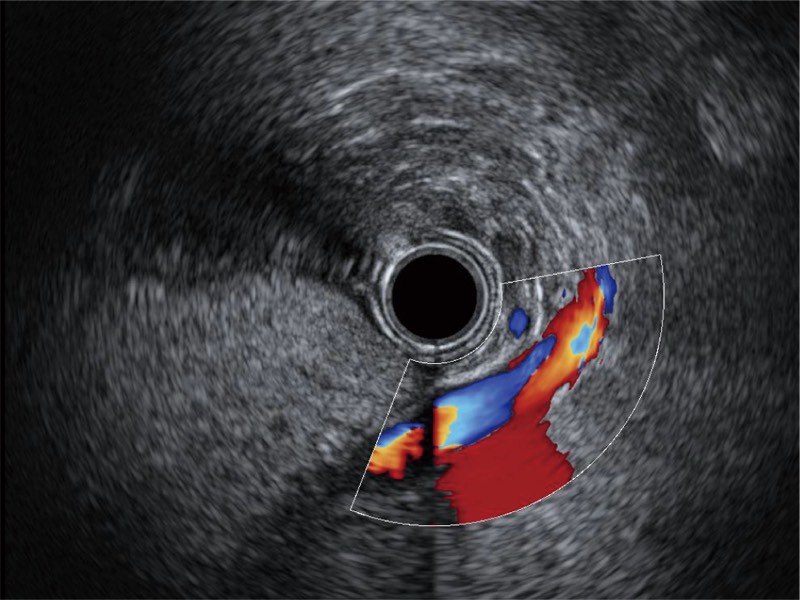

• 清晰显示胆总管及周围血管分布